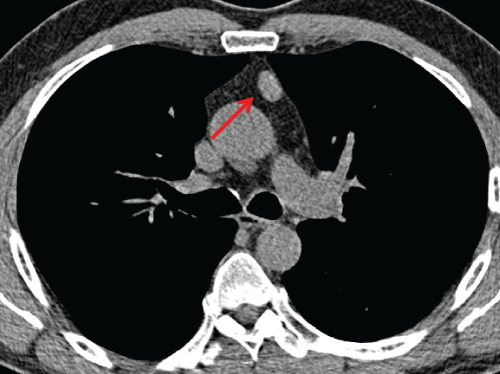

One hundred and thirty four (8.5%) exhibited findings of little or no clinical significance (category 1) for prevalence of 8.5 %. There was no change in size or attenuation of findings in any subject in category 1 on two subsequent annual screening CT scans. Incidental CT findings of variable clinical significance (category 2) were demonstrated in 44 out of 1572 subjects for prevalence rate of 2.8 %. One anterior mediastinal nodule increased in size and two cases of thyroid hypodensities were lost to follow-up in category 2. The findings in the remaining 41 did not change over two subsequent annual CT scans. The majority of incidental findings in category 1 and 2 were stable over a two year period (Figure 1, Figure 2 and Figure 3).

Figure 3: 67-year old man with a nodule in anterior mediastinum (arrow). Axial LDCT image shows a 1-cm soft tissue nodule in anterior mediastinum which was stable over 3 annual screening CT scans